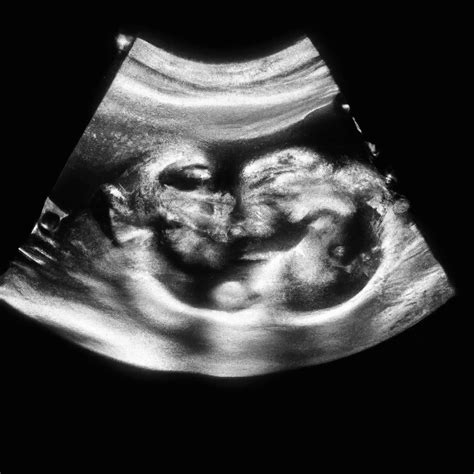

After the 32 weeks pregnant sonogram, the sonographer will review the images and measurements with you. Here are some key points to look out for:

• Growth Percentiles: The baby's measurements will be compared to standard growth charts to determine if the baby is growing at an appropriate rate.

• Placental Position: The sonographer will explain the position of the placenta and whether it is low-lying or anterior (in front of the baby).

• Amniotic Fluid Levels: The amount of amniotic fluid will be categorized as normal, low, or high, and the implications will be discussed.

• Baby's Position: The baby's position will be noted, and any potential issues related to the position will be addressed.

If any abnormalities are detected, your healthcare provider will discuss the next steps, which may include additional testing or monitoring.